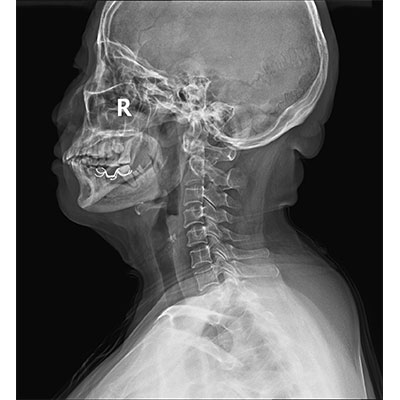

以微知形 為愛(ài)負責 微劑量 極速曝光 PLX8500E/F

● 采用自主研發(fā)的技術(shù),在保證優(yōu)質(zhì)圖像的前提下,大大降低X射線(xiàn)劑量,用心呵護醫護工作者及患者的健康。

● 短曝光時(shí)間,便于老年人、兒童、殘疾人進(jìn)行臨床拍攝。避免這類(lèi)群體因不能有效控制身體運動(dòng)等因素造成的運動(dòng)偽影,提高攝片質(zhì)量及效率。